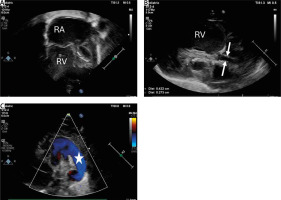

The main indications for HP were poor general condition with severe cardiac compromise (n = 12), multi-organ dysfunction (n = 12), extremely hypoplastic ascending aorta (n = 3) (Figure 1) with a diameter of less than 3 mm, and low body weight (below 3 kg in 3 neonates). The procedures were performed at an average age of 8.6, SD 9.2 days, although in 4 children urgent interventions were necessary after birth due to the critical condition. The mean body weight at the operation was 3.3, SD 0.3 kg.

Figure 1

Transthoracic echocardiography (TTE) showing hypoplastic left heart syndrome. A – TTE. 2DE. Apical 4 chamber view showing dilated right atrium and right ventricle and extremely hypoplastic left ventricle with fibroelastosis. B – Parasternal longitudinal axis. Aortic valve atresia with extremely hypoplastic ascending aorta (2.7 mm) (white arrows) and bulbus of the aorta (4.2 mm). C – Parasternal short axis view with color Doppler flow showing wide patent arterial duct (white star) with right-to-left shunting

RA – right atrium, RV – right ventricle.